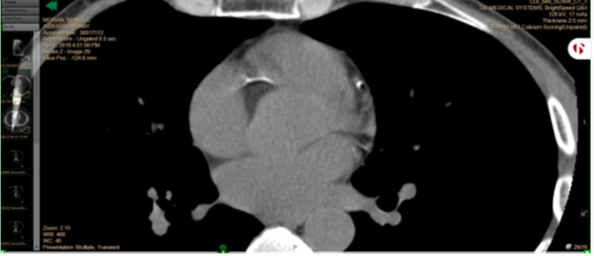

No cardiac events happened during the study period. The right coronary artery calcium score dropped from 39 in 2019 to 21 in 2020. Circumflex calcium score dropped from 9 to 2. In the CT images below, left upper cardiac artery is the right coronary artery; right lower artery is the circumflex.